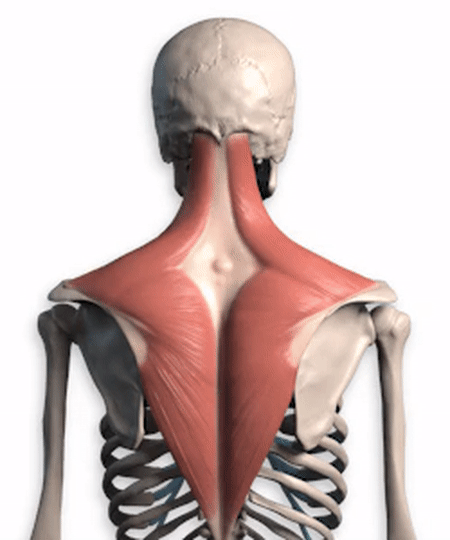

Comme indiqué ci-dessus, ce muscle est anatomiquement ce que l'on appelle un "levator scapulae (anatomie)". Il se développe d'une part sur l'apophyse transverse des vertèbres cervicales 1 à 4, et d'autre part à l'endroit même où se trouve le point douloureux (l'angle supérieur interne de l'omoplate). Sa fonction principale est la suivante :Lorsque la fin du point de douleur est fixéeLa tête et le cou sont inclinés vers l'arrière lorsque les deux côtés sont contractés et raccourcis.Lorsque la tête est baissée pendant une longue période, elle s'étire progressivement lorsque la tête est tirée vers l'avant, jusqu'à ce qu'à la limite, lorsqu'il n'est plus possible de l'étirer davantage, il y ait une douleur à l'angle supérieur interne de l'omoplate, à l'extrémité stationnaire.。

Beaucoup de mes amis pensent queUn cou est un cou, une épaule est une épaule, un dos est un dosque les trois n'ont pas grand-chose à voir l'un avec l'autre, en fait, cette idée est biaisée, de la part des étudiants en médecine, nous devrions prendre l'exemple de l'école de médecine.颈, épaule, dosRegardez-le comme un seul, à partir d'un seul muscle, et donnez une brève analyse de ce muscle, qui est lele muscle trapèze (du haut du dos et du cou)。

Si vous regardez de près, vous verrezCe trapèze.inclureBase du crâne, cou, épaules et dosLes muscles trapèzes des deux côtés sont étroitement liés et forment ensemble une structure rhomboïde, qui est essentielle au maintien de l'équilibre de la colonne vertébrale.Stabilisation du dosIl joue un rôle très important dans l'accomplissement de multiples activités au niveau du cou, des épaules et du dos.Le muscle trapèze est divisé en faisceaux supérieur, moyen et inférieur, et les différentes parties de la contraction permettent d'effectuer des mouvements différents。